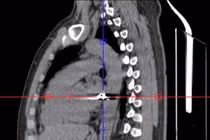

Ngay lập tức, các y, bác sĩ cho bệnh nhân tiến hành làm cận lâm sàng khẩn cấp: Xét nghiệm máu, siêu âm, chụp CT scanner bụng. Sau đó, các y, bác sĩ Khoa Cấp cứu và Khoa Ngoại tiêu hóa, Khoa Ngoại tổng hợp cùng hội chẩn chuyên môn, chẩn đoán bệnh nhân bị đa chấn thương ngực bụng, chảy máu ổ bụng vỡ gan/gãy xương sườn 5, 6, 7, 8, 9, 10, 11 bên phải.

Ê-kíp quyết định mổ cấp cứu ngay. Quá trình phẫu thuật trong bụng bệnh nhân lượng máu mất khoảng 2.800 ml vừa máu tươi lẫn máu đông, gan vỡ dập nát hạ phân thùy V, VI, VII.

Trong quá trình phẫu thuật, các bác sĩ đã cắt bỏ phần gan vỡ dập nát, khâu gan cầm máu. Gan vỡ diện rộng, vỡ sâu nhiều hạ phân thùy, mặc dù cầm máu kỹ nhưng gan vẫn còn rỉ máu liên tục, các bác sĩ quyết định chèn gạc ép gan để cầm máu.

Tiến hành phẫu thuật lần 2, các bác sĩ lấy bỏ gạc chèn, kiểm tra gan không còn chảy máu, các cơ quan nội tạng khác không tổn thương, rửa bụng, đặt dẫn lưu gầm gan. Chèn gạc cầm máu là phương pháp tạm thời chờ mổ lại cầm máu thực thụ trong những chấn thương gan nặng độ IV, độ V, bệnh nhân mất máu nhiều, tình trạng nặng.